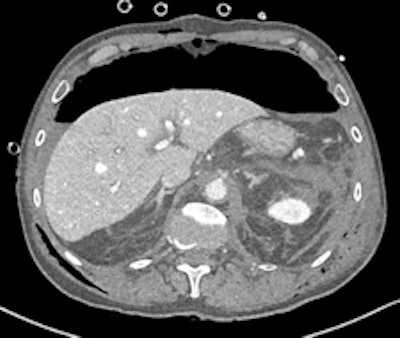

Gastroduodenal artery pseudoaneurysm in a 45-year-old man with pancreatitis and upper gastrointestinal bleed. Image courtesy of Dr. Paresh K. Desai and radiopaedia.org. radiopaedia.org/cases/gastroduodenal-artery-pseudoaneurysm.